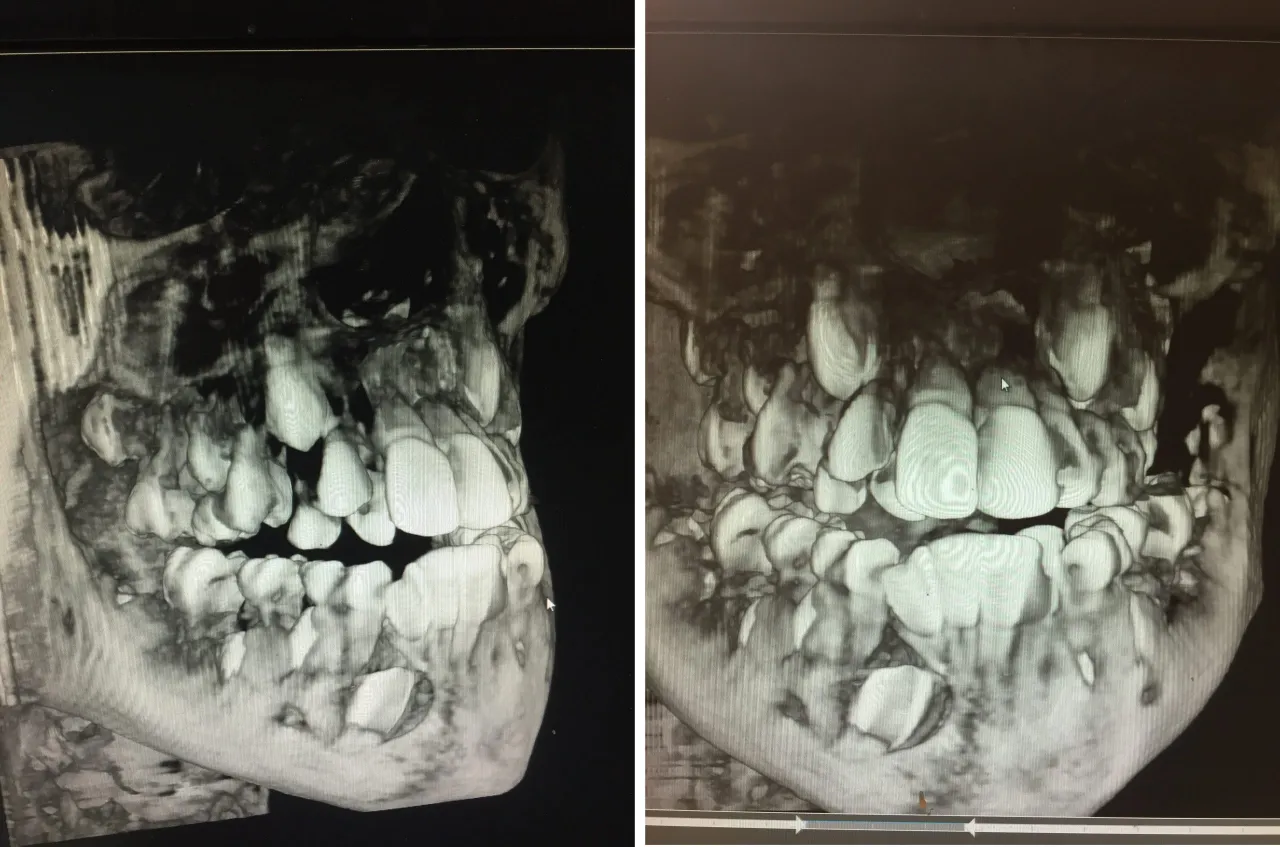

- Możliwe są anomalie liczbowe, takie jak hipodoncja (brak zębów) lub hiperdoncja (zęby nadliczbowe).

Choć standardem jest posiadanie od 28 do 32 zębów stałych, w praktyce stomatologicznej spotykamy się z różnymi odchyleniami od tej normy. Jedną z takich anomalii jest hipodoncja, czyli wrodzony brak zawiązków jednego lub kilku zębów stałych. Dotyka ona kilku procent populacji i najczęściej obserwuje się brak drugich przedtrzonowców oraz bocznych siekaczy. Przyczyny hipodoncji mogą być różnorodne od czynników genetycznych, dziedziczonych po rodzicach, po środowiskowe, takie jak urazy czy infekcje w okresie rozwoju zębów. To problem, który wymaga uwagi, ponieważ może wpływać na zgryz i estetykę.

Zupełnie przeciwnym zjawiskiem jest hiperdoncja, czyli obecność zębów nadliczbowych. Oznacza to, że w jamie ustnej pojawia się więcej zębów niż przewiduje norma. Zęby nadliczbowe mogą wyrzynać się w różnych miejscach, często powodując stłoczenia, problemy ze zgryzem, a nawet zatrzymanie wyrzynania się prawidłowych zębów. Najczęściej występującym zębem nadliczbowym jest tzw. mezjodens, który zwykle lokalizuje się między górnymi siekaczami i często jest wykrywany przypadkowo podczas rutynowych badań rentgenowskich.